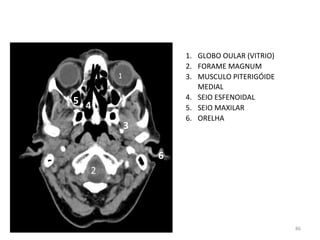

1. GLOBO OULAR (VITRIO)

2. FORAME MAGNUM

3. MUSCULO PITERIGÓIDE

MEDIAL

4. SEIO ESFENOIDAL

5. SEIO MAXILAR

6. ORELHA